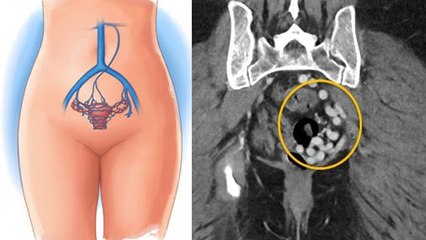

Stomach pain is a very common problem. We cannot call abdominal pain as a sign or symptom of any particular disease. This is because when any part of our body is affected, it also affects other organs. There are many types of colic, which we can divide on the basis of which part of the stomach is hurting. But today we will talk only about upper stomach pain. Upper abdominal pain occurs due to many reasons.